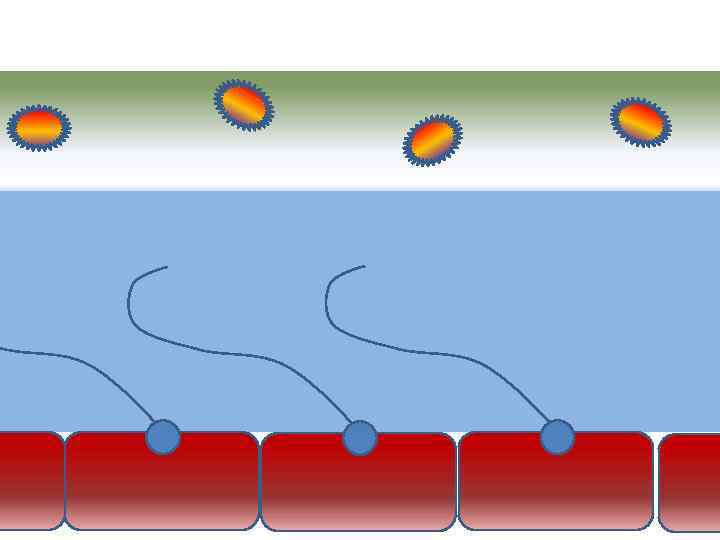

Факторы риска Недостаточное увлажнение дыхательной смеси Высушивание трахеи и бронхов

Факторы риска Недостаточное увлажнение дыхательной смеси Высушивание трахеи и бронхов

Факторы риска Недостаточное увлажнение дыхательной смеси ! Слизистая оболочка трахеи и бронхов обязательно должна быть укрыта секретом

Факторы риска Недостаточное увлажнение дыхательной смеси ! Слизистая оболочка трахеи и бронхов обязательно должна быть укрыта секретом

Факторы риска Недостаточное увлажнение дыхательной смеси • естественное удаление бактерий • состояние эпителия трахеи и бронхов

Факторы риска Недостаточное увлажнение дыхательной смеси • естественное удаление бактерий • состояние эпителия трахеи и бронхов

Оптимальное увлажнение 37°С, 44 мг/л Оптимальная влажность • Уменьшает время нахождения патогенной флоры в легком

Оптимальное увлажнение 37°С, 44 мг/л Оптимальная влажность • Уменьшает время нахождения патогенной флоры в легком

Движение клеток реснитчатого эпителия Движение вперед 1 – 3 Обратное движение 4 – 8

Движение клеток реснитчатого эпителия Движение вперед 1 – 3 Обратное движение 4 – 8

Оптимальное увлажнение Достаточная продукция слизи Хороший транспорт Экономит энергию и воду Защитная функция

Оптимальное увлажнение Достаточная продукция слизи Хороший транспорт Экономит энергию и воду Защитная функция

Механизм защиты легкого Слизь (зеленый цвет) нейтрализует и связывает патогенную флору(синий цвет) Слизь – это барьер между клетками и патогенной флорой Слизь – это транспортное средство

Механизм защиты легкого Слизь (зеленый цвет) нейтрализует и связывает патогенную флору(синий цвет) Слизь – это барьер между клетками и патогенной флорой Слизь – это транспортное средство